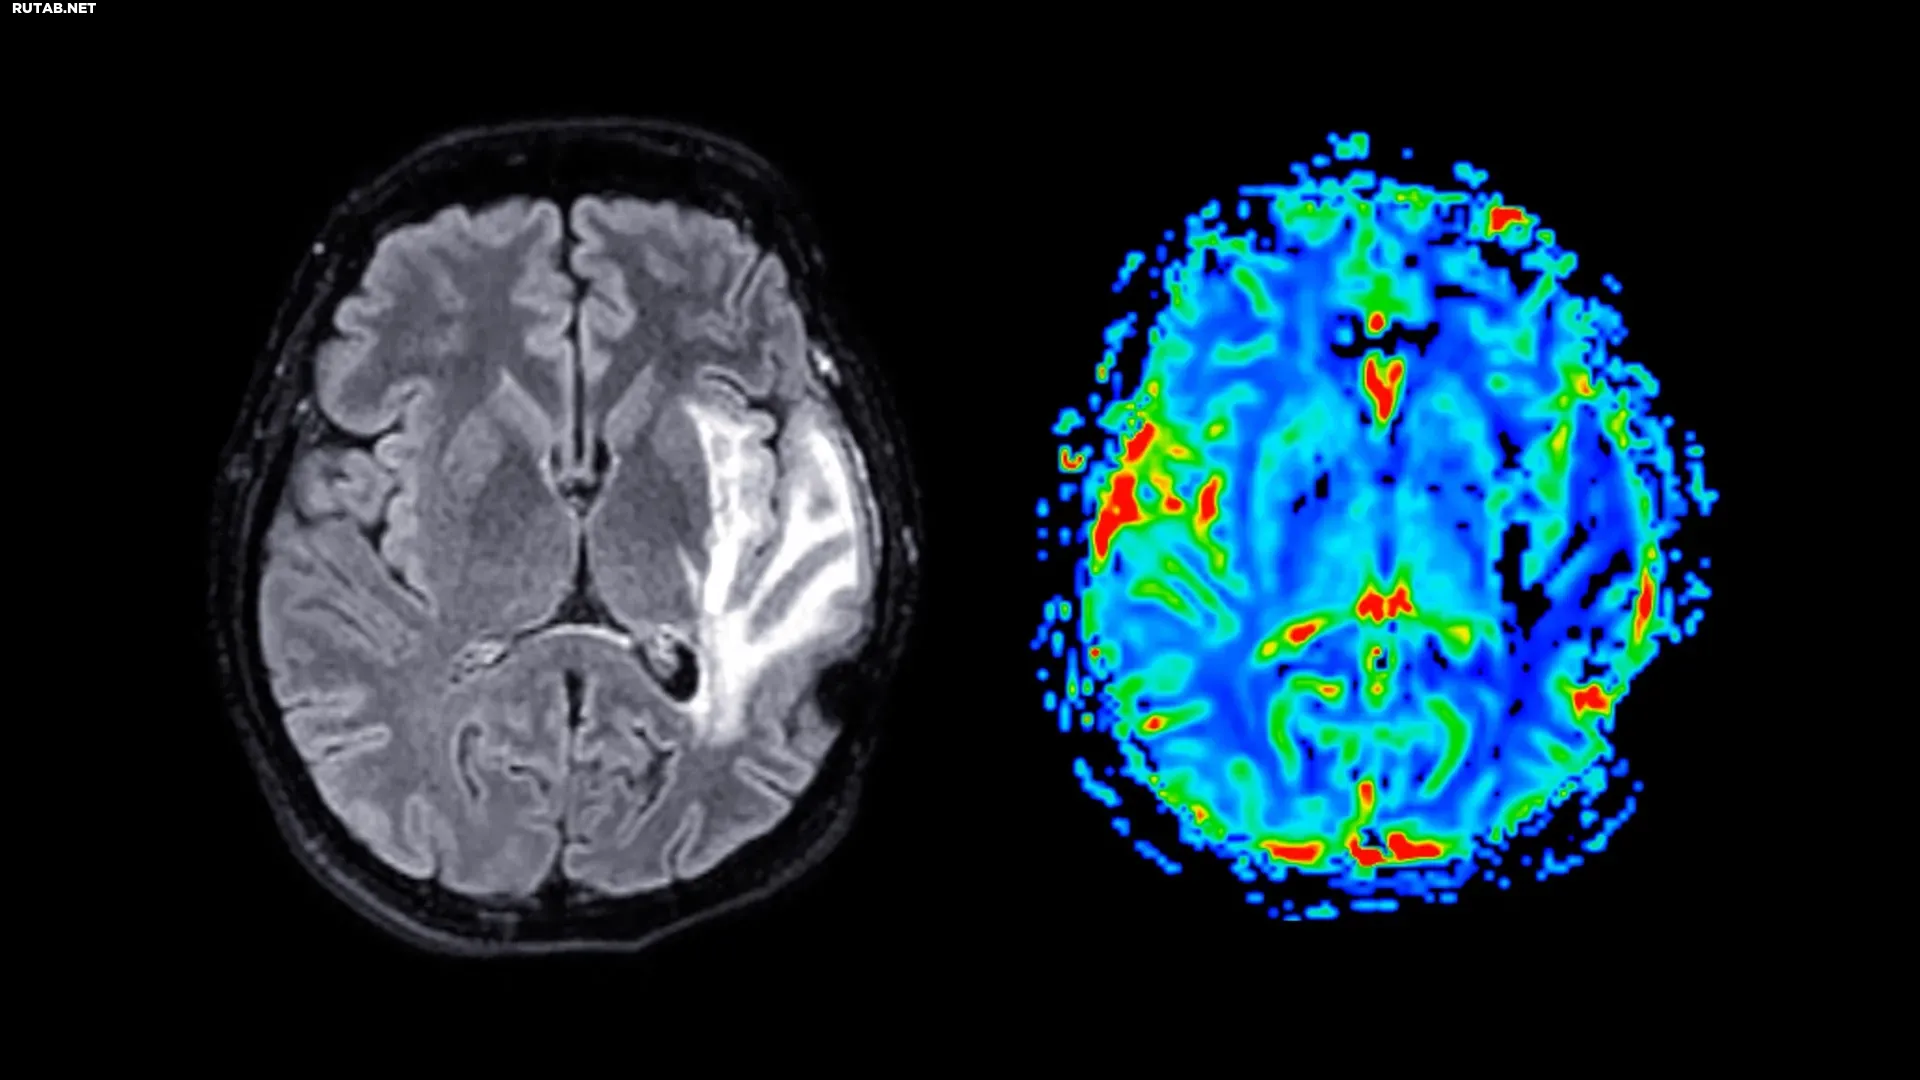

Деменция, включая болезнь Альцгеймера и сосудистую деменцию, представляет собой серьёзную глобальную проблему для здоровья, и на сегодняшний день лекарства от неё не существует.